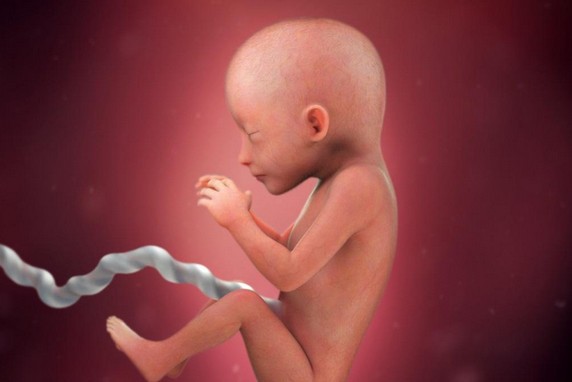

الأسبوع الثالث عشر

مراحل نمو الجنين بالصور

خلال هذا الأسبوع تبدأ المشيمة بالنمو والتطور ويعمل على إمداد الجنين بالغذاء والأكسجين ويبدأ إنتاج هرمونات الأستروجين والبروجسترون وكلاهما يساعدان على ثبات الحمل، تبدأ أمعاء الجنين بالتكون ويبدأ الجنين بتكوين البول الخاص به ومن ثم تصريفه للسائل الذي يحيط بالجنين.

الاسبوع الرابع عشر

يبدأ الشعر بالنمو في رأسه وعلى جسده بالتدريج ويظل على جسمه قبل الولادة ويسقط عند ولادته ويكتمل نمو الأعضاء التناسلية خلال هذا الأسبوع ولكن لا يمكن رؤيتها أثناء الفحص بجهاز السونار، ويكتمل نمو الغدة الدرقية وتبدأ بإنتاج هرموناتها ويبلغ وزن الجنين بنهاية هذا الأسبوع 45 جم.